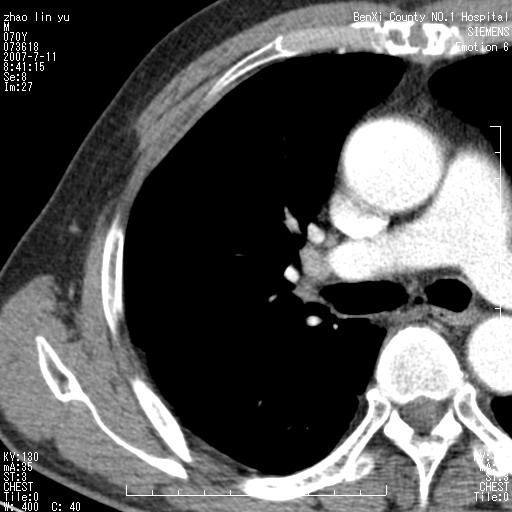

以下是引用王靖旗在2007-7-10 17:12:00的发言:[br] 男、70、咳嗽两个月,半年前换瓣手术,胸片未见异常,于昨天行x片发现右肺上野大片影,行ct扫描,这里是减薄图像,余肺正常。明天晚上会有增强扫描片,到时我会上传。[br][br] 冠状位请大家细看,应该是有意义的,[br][br] 请大家先看平扫发表意见。[br][br]

以下是引用zhangzhongshou在2007-7-10 21:43:00的发言:[br]右肺上叶周围型肺癌,以孤立型细支气管肺泡癌可能性大。